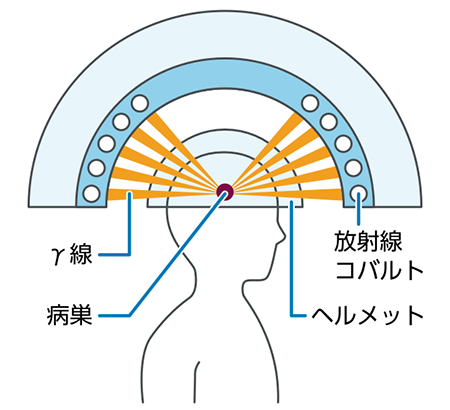

脳転移の数が少ないときは、放射線治療や外科手術が行われます。以前は外科手術が主流でしたが、最近は患者さんの負担が小さい放射線治療が優先的に行われています。

放射線治療には、転移巣をピンポイントに照射する定位放射線照射と、脳全体に放射線を当てる全脳照射があります。定位放射線照射には、1回照射の定位手術的照射(ガンマナイフ)と複数回照射の定位放射線治療があります。どの方法を行うかは、転移の数や部位によって決められます。